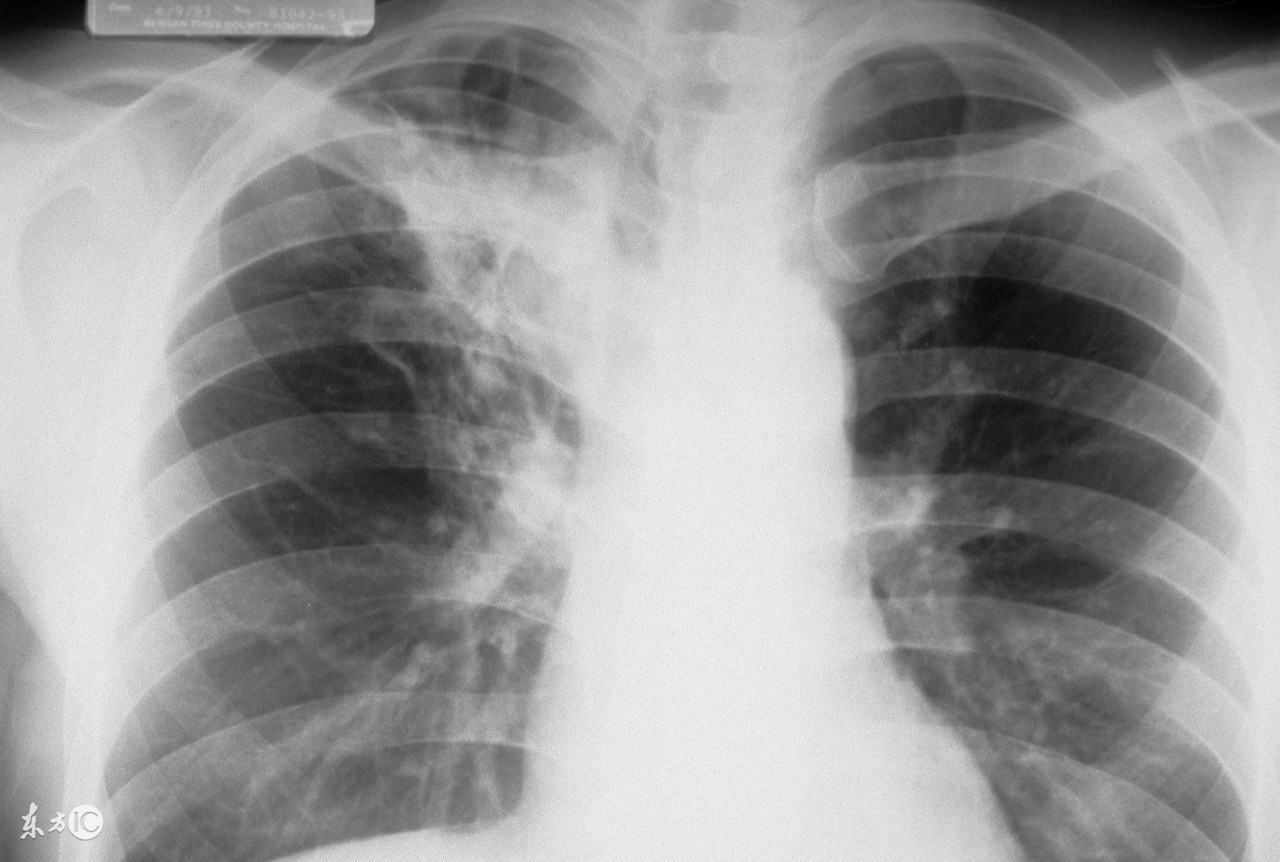

为了更准确的诊断肺结核,一般都要做肺结核皮试,通过做这个检查可以明确人体带菌的概率,肺结核皮试出现双圈是什么意思?阳性和阴性有什么不同?

肺结核皮试结果判断中,如果皮肤出现双圈,是强阳性的表现。现在向大家介绍一下皮试的具体情况。